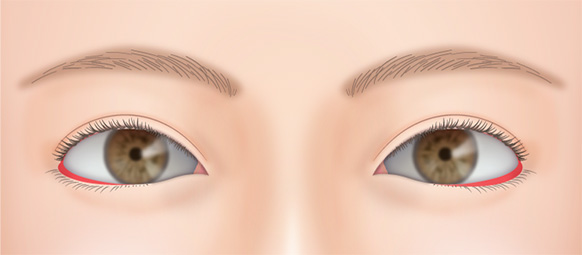

二重の幅が広くなり過ぎて、いかにも整形っぽい目になることがあります。

切開法の場合、前回の手術の切開線の傷跡の上(眉毛側)で新たに作る二重のラインに沿って切開し、幅を広げ、自然な形にすることができます。

元々まぶたの開きが悪い人は眼瞼下垂手術を併用して目を開けた状態での二重の幅を狭くする修正手術も可能です。

蒙古ひだが強く張っている場合は、目頭切開をすると平行型になる場合があります。

無理に幅広の二重を作った場合、腫れが半年以上も続き、ハム目のようになる場合があります。

前回の手術で皮膚を大きく切除していていなければ幅の狭い二重に修正することが可能です。